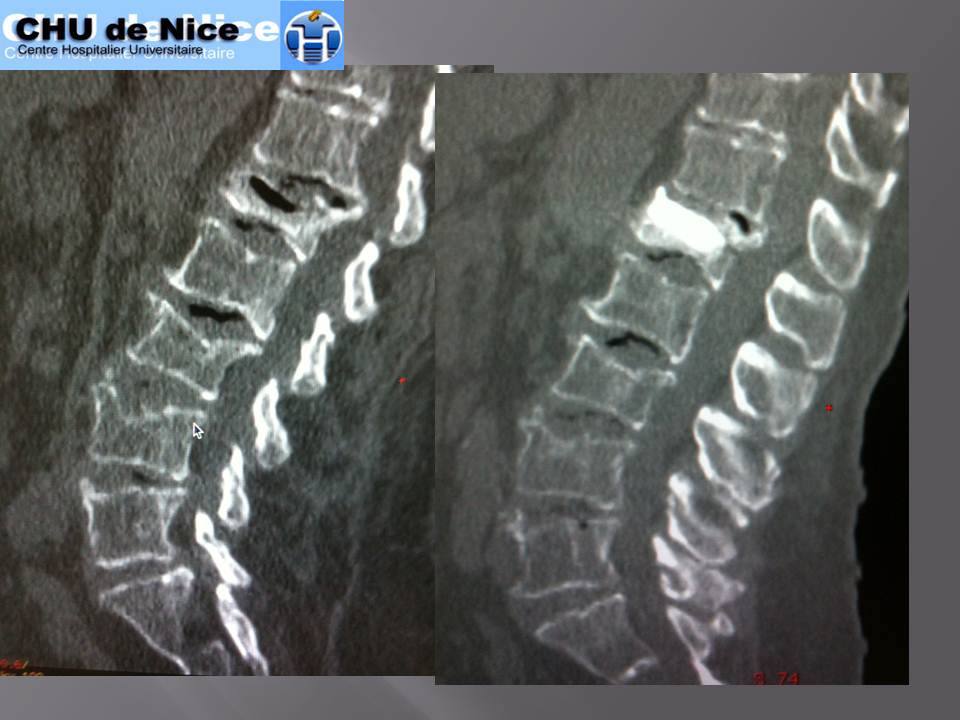

• Vertebroplastie et burst A2